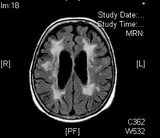

Eine Kernspintomographie des Kopfes zeigt, ob bereits Durchblutungsstörungen der großen oder kleinen Hirngefäße stattfinden. Das Risiko für Schlaganfall durch Herzerkrankungen wird in der Kooperation mit Kardiologen geklärt. Die Therapie mit Medikamenten zielt darauf, einen Schlaganfall oder weitere Schlaganfälle zu verhindern. Wir legen besonderen Wert auf die Schlaganfallvorsorge. Mit einer rechtzeitigen Analyse aller individuellen Risikofaktoren ist ein Schlaganfall sehr oft vermeidbar.